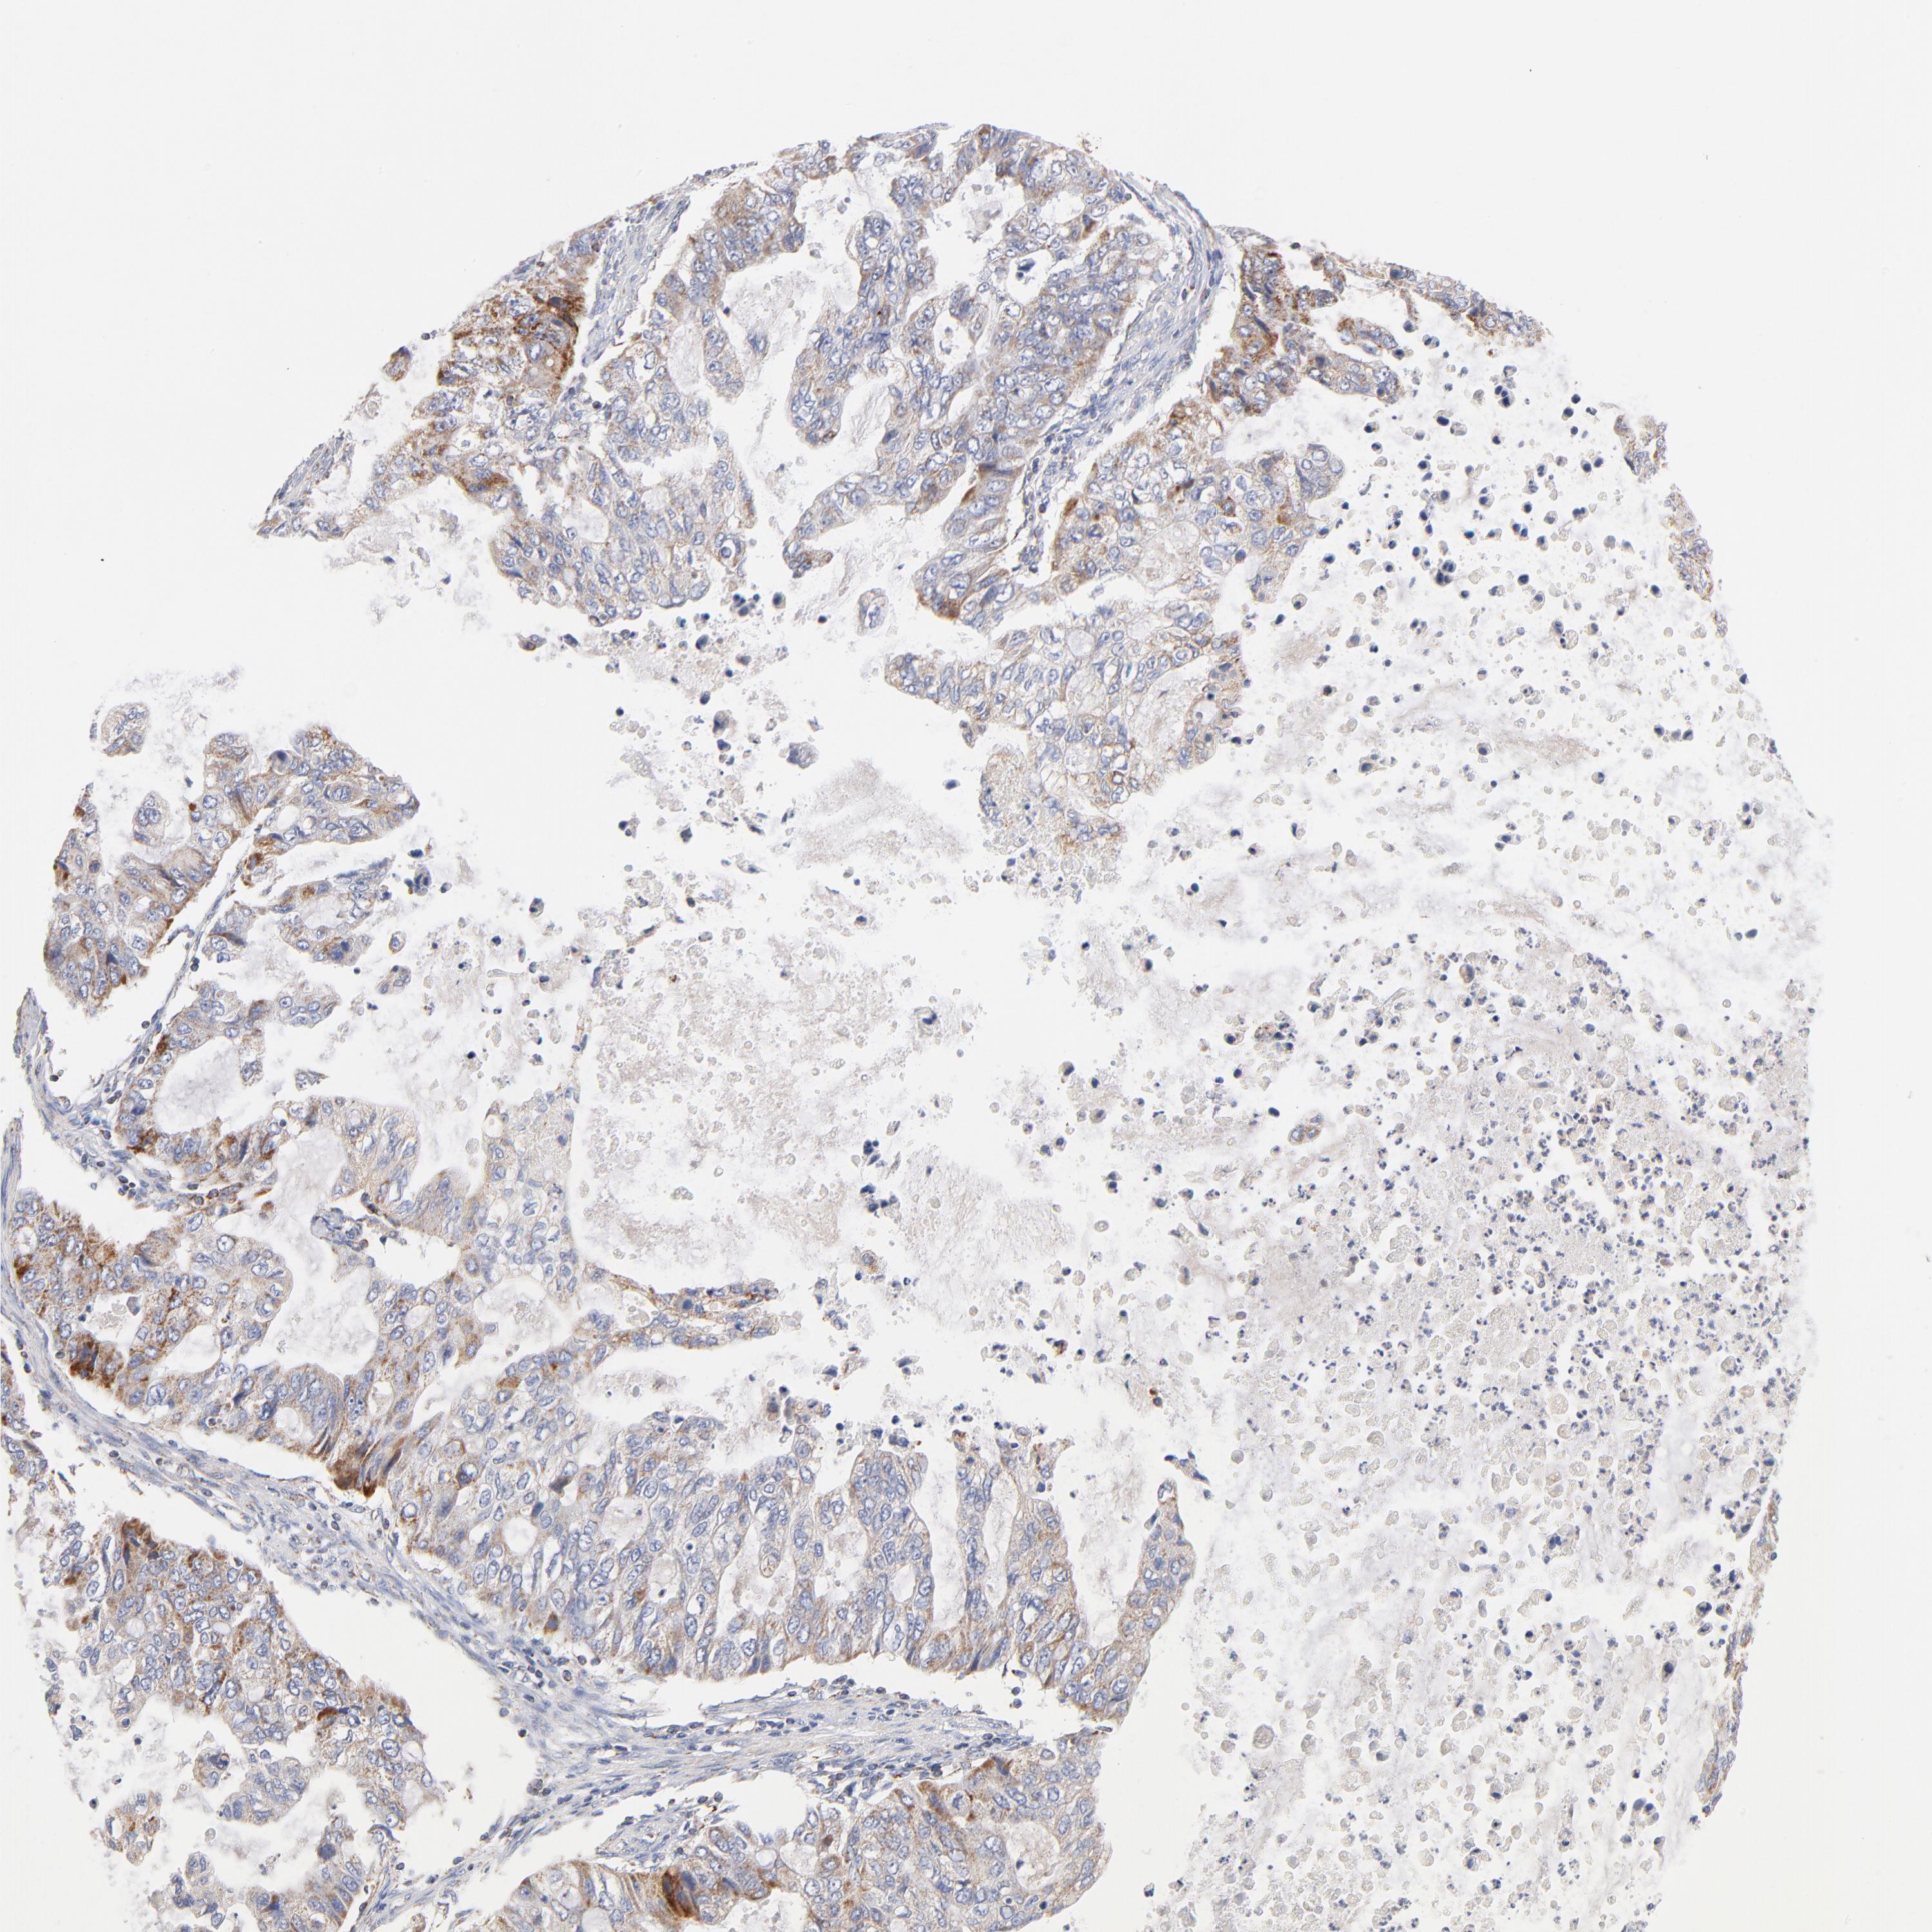

STOMACH CANCER - Protein expressioni

A mouse-over function shows sample information and annotation data. Click on an image to view it in a full screen mode. Samples can be filtered based on level of antibody staining by selecting one or several of the following categories: high, medium, low and not detected. The assay and annotation is described here.

Note that samples used for immunohistochemistry by the Human Protein Atlas do not correspond to samples in the TCGA dataset.

Antibody stainingi

Antibody staining in the annotated cell types in the current human tissue is reported as not detected, low, medium, or high, based on conventional immunohistochemistry profiling in selected tissues. This score is based on the combination of the staining intensity and fraction of stained cells.

Each image is clickable and will lead to virtual microscopy that enables deeper exploration of all samples and also displays staining intensity scores, fraction scores and subcellular localization as well as patient and tissue information for each sample.

Antibody HPA040786

Antibody CAB003782

Staining

High

Medium

Low

Not detected

Intensity

Strong

Moderate

Weak

Negative

Quantity

>75%

75%-25%

<25%

None

Location

Nuclear

Cytoplasmic/membranous

Cytoplasmic/membranous,nuclear

Adenocarcinoma, NOS